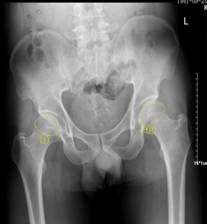

新技術(shù):瀘州市中醫(yī)院成功開展富血小板血漿(PRP)術(shù)——早期股骨頭壞死患者福音股骨頭壞死是一種原因不明的常見骨科疾病,根據(jù)不同的發(fā)病程度和部位分區(qū)有不同的治療方法。近日,瀘州市中醫(yī)院成功開展的富血小板血漿微創(chuàng)手術(shù)(簡稱:PRP)為早期股骨頭壞死患者帶來福音,同時也為保髖治療增添了新的治療方法。診斷:...